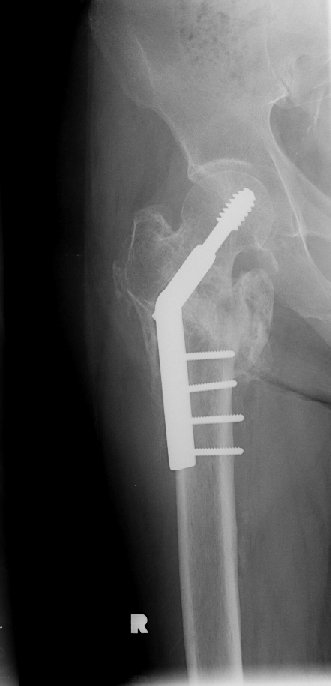

Return to Intertrochanteric Fracture